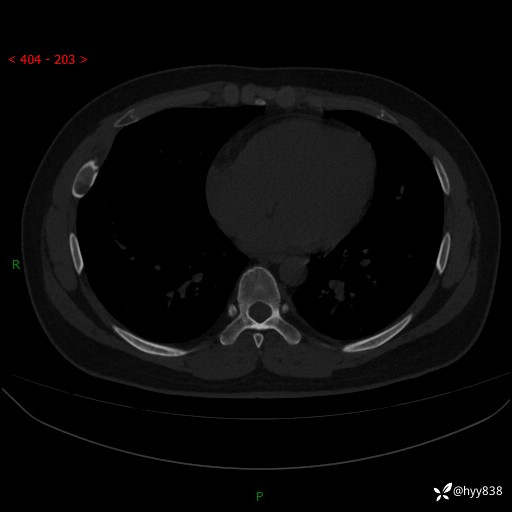

胸部CT平扫